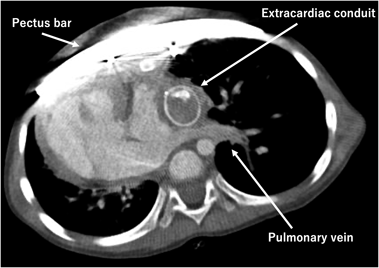

Preoperative computed tomography scan revealed compression of the right atrium and the left pulmonary vein by a depressed sternum, with the Haller Index of 6.25 (Fig. 1).

The postoperative course was uneventful, and the patient was discharged home on the 15th postoperative day. Postoperative computed tomography scan revealed repaired pectus excavatum without compression of the conduit, the IVC, nor the pulmonary veins. Haller index improved to 2.80 (Fig. 3).